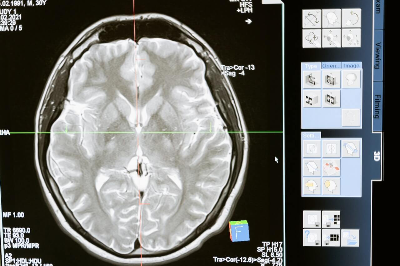

뇌 병변의 진단은 일반적으로 자기공명영상(MRI) 또는 컴퓨터 단층촬영(CT) 스캔과 같은 영상 검사와 함께 의료 전문가의 철저한 병력 및 신경학적 검사를 통해 이루어집니다.